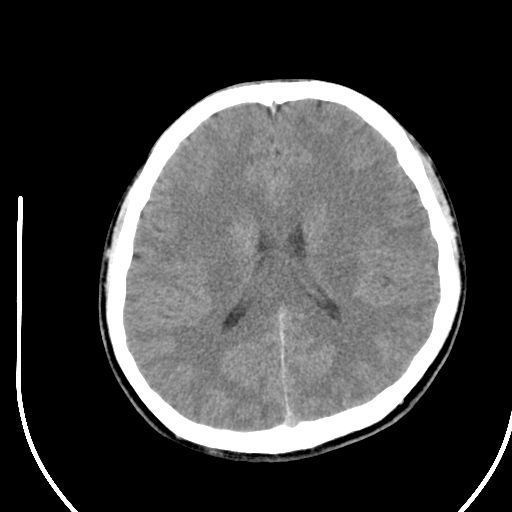

标题: CT28158:男,27Y。头痛数月,左顶叶血管瘤。 [打印本页]

标题: CT28158:男,27Y。头痛数月,左顶叶血管瘤。

海绵状血管瘤

考虑左顶叶海绵状血管瘤,建议mr检查。

左侧额叶海绵状血管瘤可能性大;建议行mri检查。

考虑血管畸形,因其周可见水肿,不除外感染性病灶。建议mri检查。